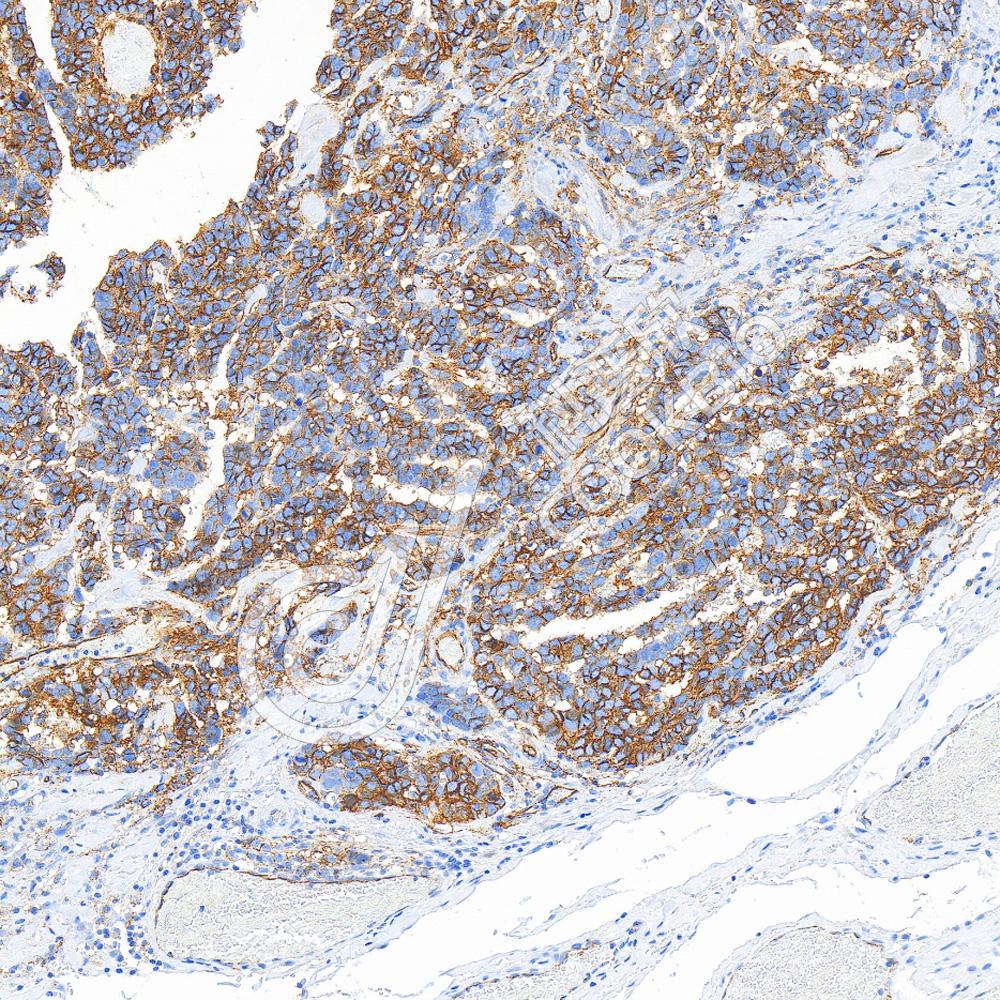

IHC检测CD5蛋白(货号 K1334080).

样品: 小鼠脾, 4%多聚甲醛 (货号KSG1101) 固定12-24小时.

抗原修复: 柠檬酸抗原修复液(干粉, pH 6.0) (KSG1201), 98℃, 20分钟.

—抗: 1: 2100稀释, 4℃ 孵育过夜.

二抗: S-vision免疫组化多聚二抗(山羊抗兔),即用型 (货号KB3906), 室温孵育20分钟.